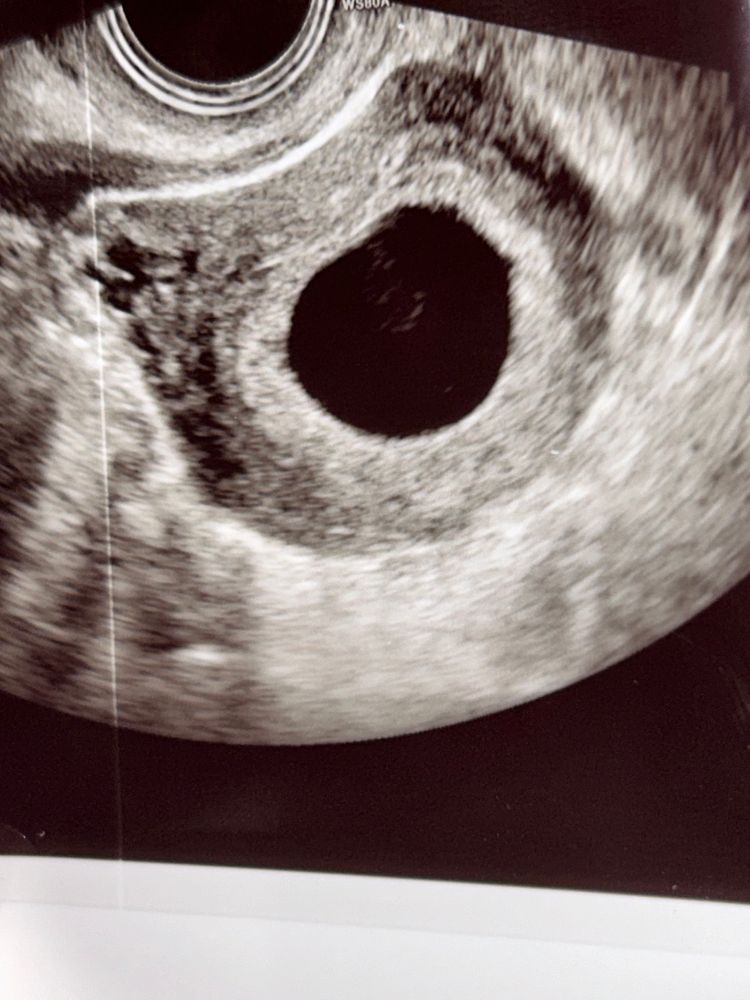

Что это в плодном яйце ?

К сожалению, но при таком размере ПЯ жм уже четко должен быть виден. На фото нет четкого изображения, это могут быть взвеси. Жм виден на узи начиная с 6мм плодного яйца, а эмбрион визуализируется, когда плодное яйцо становится больше 16-17мм. Я посмотрела свои узи на таком сроке. вот в 6н4д пя было 19мм и уже даже эмбрион с сердцебиением увидели.

Тата Савина, артефакты на УЗИ, взвеси и т. п. Если был бы жм, его было бы видно и на другим снимках. Тем более жм не висит вот так просто в середине пя, он находится на поверхности пя, и лишь в одной проекции в серединке можно увидеть. Но если на других снимках нет, то его нет. Ну уж узисты же не идиоты, не разглядеть жм? Это врачи с нужным образованием. Сходите в другое место, платно, если этому не доверяете.

На 1 фото очень похоже на жм

Маргарита, мне ставили вчера срок 6 недель и анембрению , но я жду еще недельку - две и сделаю узи , узисты ничего не видят в плодном ( а домой приехала смотрю и на одном фото узи этот кружочек а на двух ниже уже не видно

Тата Савина, ну на этом фото прямо классика "кольцо с бриллиантом"

Увидела, что 21 мм. Повторите узи через 5 дней.

Размер ПЯ какой? Если больше 25 мм-Надежды нет. Это пустое плодное яйцо. А наличие взвеси и неоднородных включений еще больше свидетельствует в пользу НБ.

Ася, у меня 21 мм плодное яйцо

Пустое плодное яйцо 😞 К 6 неделям уже должен визуализироваться эмбриончик.